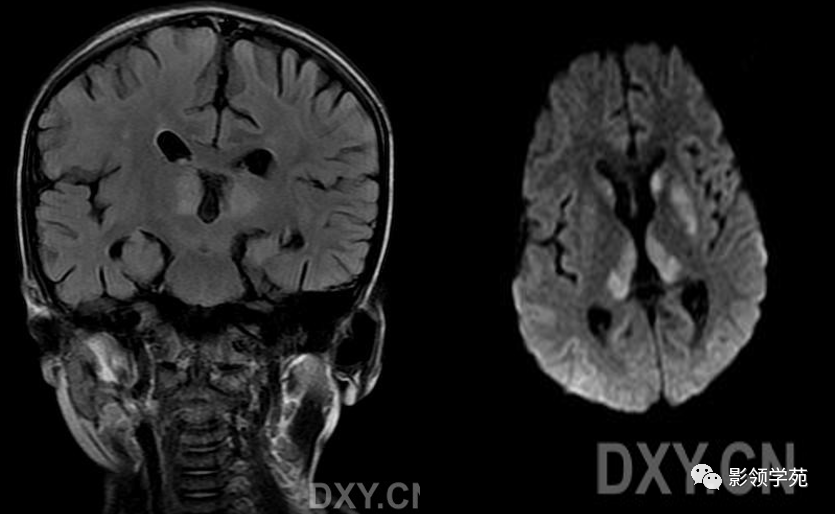

wernicke脑病的影像诊断

图片尺寸1080x608